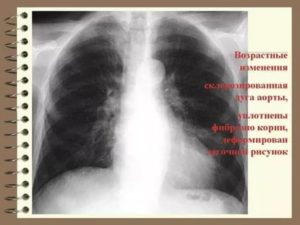

Уплотнение корней — один из наиболее часто встречающихся рентгенологических синдромов, который врач-рентгенолог определяет на обзорной рентгенографии грудной полости. Что это означает: «уплотнены корни легких»? Какие заболевания и патологические состояния скрываются под этой фразой?

Чтобы определить на рентгене такой симптом, как уплотнение корней легких, в первую очередь нужно знать особенности этих образований в норме.

Как правило, увеличение и уплотнение корней легких происходят одновременно. Обычно изолированное уплотнение указывает на хронический процесс, когда повышено количество соединительной ткани в корнях легких.

Как правило, уплотнение корней легких наблюдается совместно с их расширением и может быть обусловлено теми же причинами.

Справочно. Уплотнением называют более выраженную, чем в норме, интенсивность тени. В редких случаях корни легких уплотнены при нормальном диаметре их тени.

Изолированное уплотнение свидетельствует о хроническом процессе. Чаще всего эта патология встречается при хронических воспалениях бронхиального дерева, когда часть их стенки замещается соединительной тканью. При этом расширения тени не будет, но она станет более интенсивной.